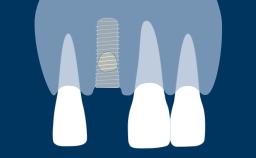

This deficit reduces the distance between the maxillary sinus floor and the alveolar process, so that reconstructing the vertical bone height may be a prerequisite for placement of dental implants of the correct dimensions and in the ideal three-dimensional position while respecting anatomical structures.

Sinus floor elevation is a predictable procedure for vertical bone augmentation in the posterior maxilla that compensates for inadequate bone height. Grafting material is placed into the sinus to increase available bone height and to facilitate the placement of implants of the desired dimensions and in the correct prosthetically driven positions.